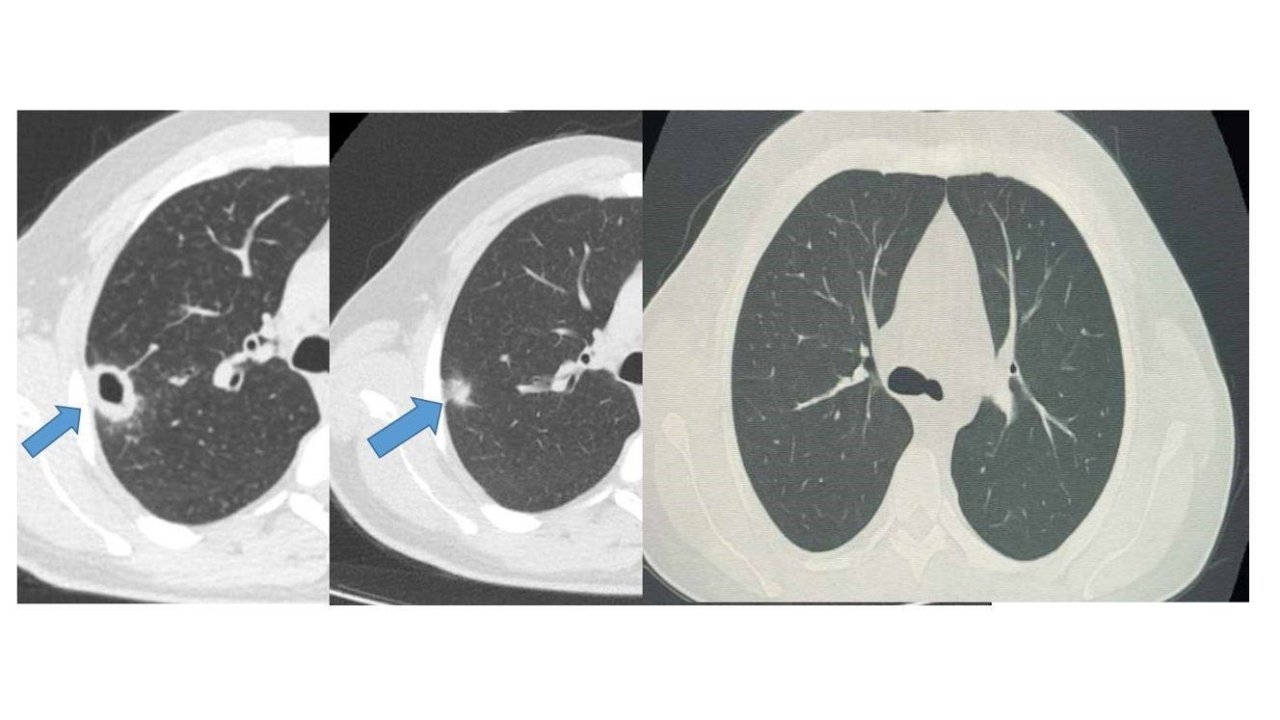

Bayburt Devlet Hastanesine öksürük ve balgam şikayetiyle başvuran 50 yaşındaki hastanın akciğerinde kitle benzeri bir doku tespit edildi. Yapılan tetkikler sonucu ciddi bir hastalık olmadığı belirlenen hasta, erken tanı ve doğru tedavi sayesinde sağlığına kavuştu.Göğüs Hastalıkları Uzmanı Uzm. Dr. Hilal Sayma tarafından muayene edilen hastaya ileri tetkik amacıyla bronkoskopi işlemi uygulandı. Bronkoskopi sonucunda lezyonun kanser veya tüberküloz gibi ciddi hastalıklarla ilişkili olmadığı belirlenerek, hasta için uygun tedaviye başlandı.İki haftalık tedavi sürecinin sonunda yapılan kontrollerde lezyonun neredeyse tamamen gerilediği görüldü. Sağlığına kavuşan hastanın taburcu edildiği ve durumunun iyi olduğu öğrenildi.

Bayburt Devlet Hastanesine öksürük ve balgam şikayetiyle başvuran 50 yaşındaki hastanın akciğerinde kitle benzeri bir doku tespit edildi.